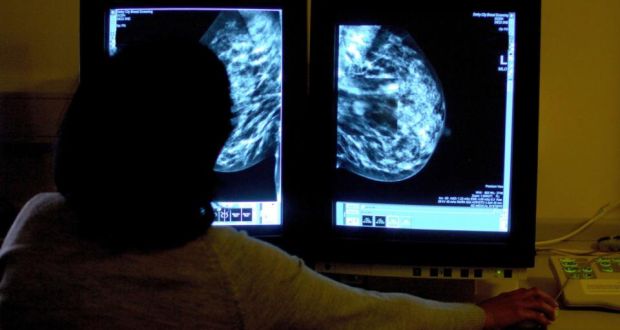

H D Nelson, dans un travail publié récemment dans les Annals of Internal Medecine, a tenté de quantifier le nombre de faux positifs et de faux négatifs ainsi que celui des imageries et des biopsies complémentaires en cas de dépistage par mammographie numérique dans la population féminine générale des Etats Unis. L’auteur s’est aussi efforcé de préciser comment ces taux variaient en fonction de différents paramètres, facteurs de risque individuels, âge et délai par rapport à la dernière mammographie notamment. Ce travail s’est basé sur les données collectées en 8 ans par le Breast Cancer Surveillance Consortium (BCSC) qui est un réseau collaboratif de différents registres de mammographies, disséminé à travers tous les USA, sous l’égide du National Cancer Institute. Les données d’imagerie ont été croisées avec celles issues des programmes régionaux de surveillance et des registres nationaux des tumeurs. La cohorte inclut 405 191 femmes, âgées de 40 à 89 ans, qui avaient eu un dépistage de routine par mammographie numérique entre 2003 et 2011 et, dans le même temps, répondu à un questionnaire à la fois sociodémographique et médical. Seules avaient été retenues les mammographies pratiquées en vue d’un dépistage, avec un délai supérieur à 9 mois par rapport à un examen antérieur, chez des femmes sans antécédent de cancer du sein, augmentation du volume mammaire ou mastectomie. Une mammographie préalable devait en outre avoir été effectuée dans les 30 mois précédents. Les résultats ont été standardisés et évalués selon la 4e édition de l’Atlas de l’American College of Radiology- BI RADS. L’analyse porte sur le nombre de faux positifs et faux négatifs ainsi que sur le nombre d’imageries et de biopsies complémentaires. Les relations avec les différents facteurs de risque et la densité mammaire ont été examinées, en séparant schématiquement les seins presque totalement graisseux ou d’allure fibro glandulaire disséminée des seins extrêmement denses ou de densité hétérogène. Enfin l’impact du délai séparant les 2 dernières mammographies a été analysé.

L’analyse des données des 5 centres US BCSC retrouve donc un taux élevé de faux positifs et d’actes techniques induits chez les femmes entre 40 et 49 ans ayant une mammographie de dépistage, ce taux tendant à diminuer par la suite. A contrario, le taux de faux négatifs est nettement plus faible et stable selon les classes d’âge. Ces taux ne semblent pas affectés par le délai séparant la mammographie de référence de l’examen antérieur. On relève également que plusieurs facteurs de risque sont significativement associés aux variations de ces taux, tels que le statut pré ou post ménopausique, un traitement hormonal de la ménopause, un IMC bas ou encore une histoire familiale de néoplasie mammaire. Ce travail confirme de plus l’impact majeur de la densité mammaire, les taux les plus bas étant notés chez les femmes avec des seins presque exclusivement graisseuse et, à l’inverse, les taux les plus élevés étant observés chez celles avec des seins très denses ou une densité hétérogène, rendant alors délicate la discrimination entre tissu sain et tissu néoplasique. Il est à signaler que les taux calculés dans ce travail sont plus élevés que ceux de la précédente analyse du BCSC, réalisée entre 2000 et 2005, auprès de plus de 600 000 femmes mais avec une technique de mammographie sur film et non de mammographie numérique.